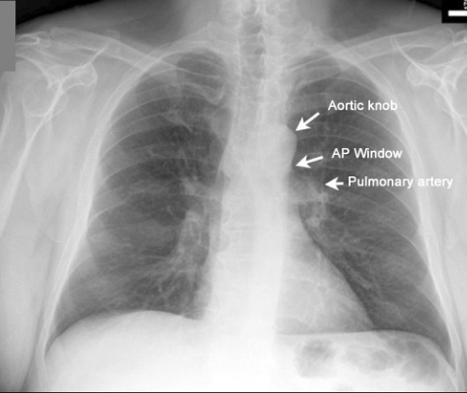

💡下行大動脈、APwindowは正常か

胸部レントゲンでは上行大動脈は肺と接していないので線とならずに見えないが、大動脈弓〜下行大動脈にかけては左肺と接しているのでレントゲンで線として見ることが出来る。

また、その際にAPwindow(大動脈肺動脈窓)もチェックしたい。

Aはaortic knob

Pはpulmonary artery

でありAPはつまり大動脈弓と肺動脈の間の隙間のことであり、正常であれば下のレントゲン写真のように空間が出来る。

APwindowの領域には縦隔リンパ節があるのでリンパ節が腫脹しているとAPwindowの凹みが盛り上がり、APwindow消失となる。